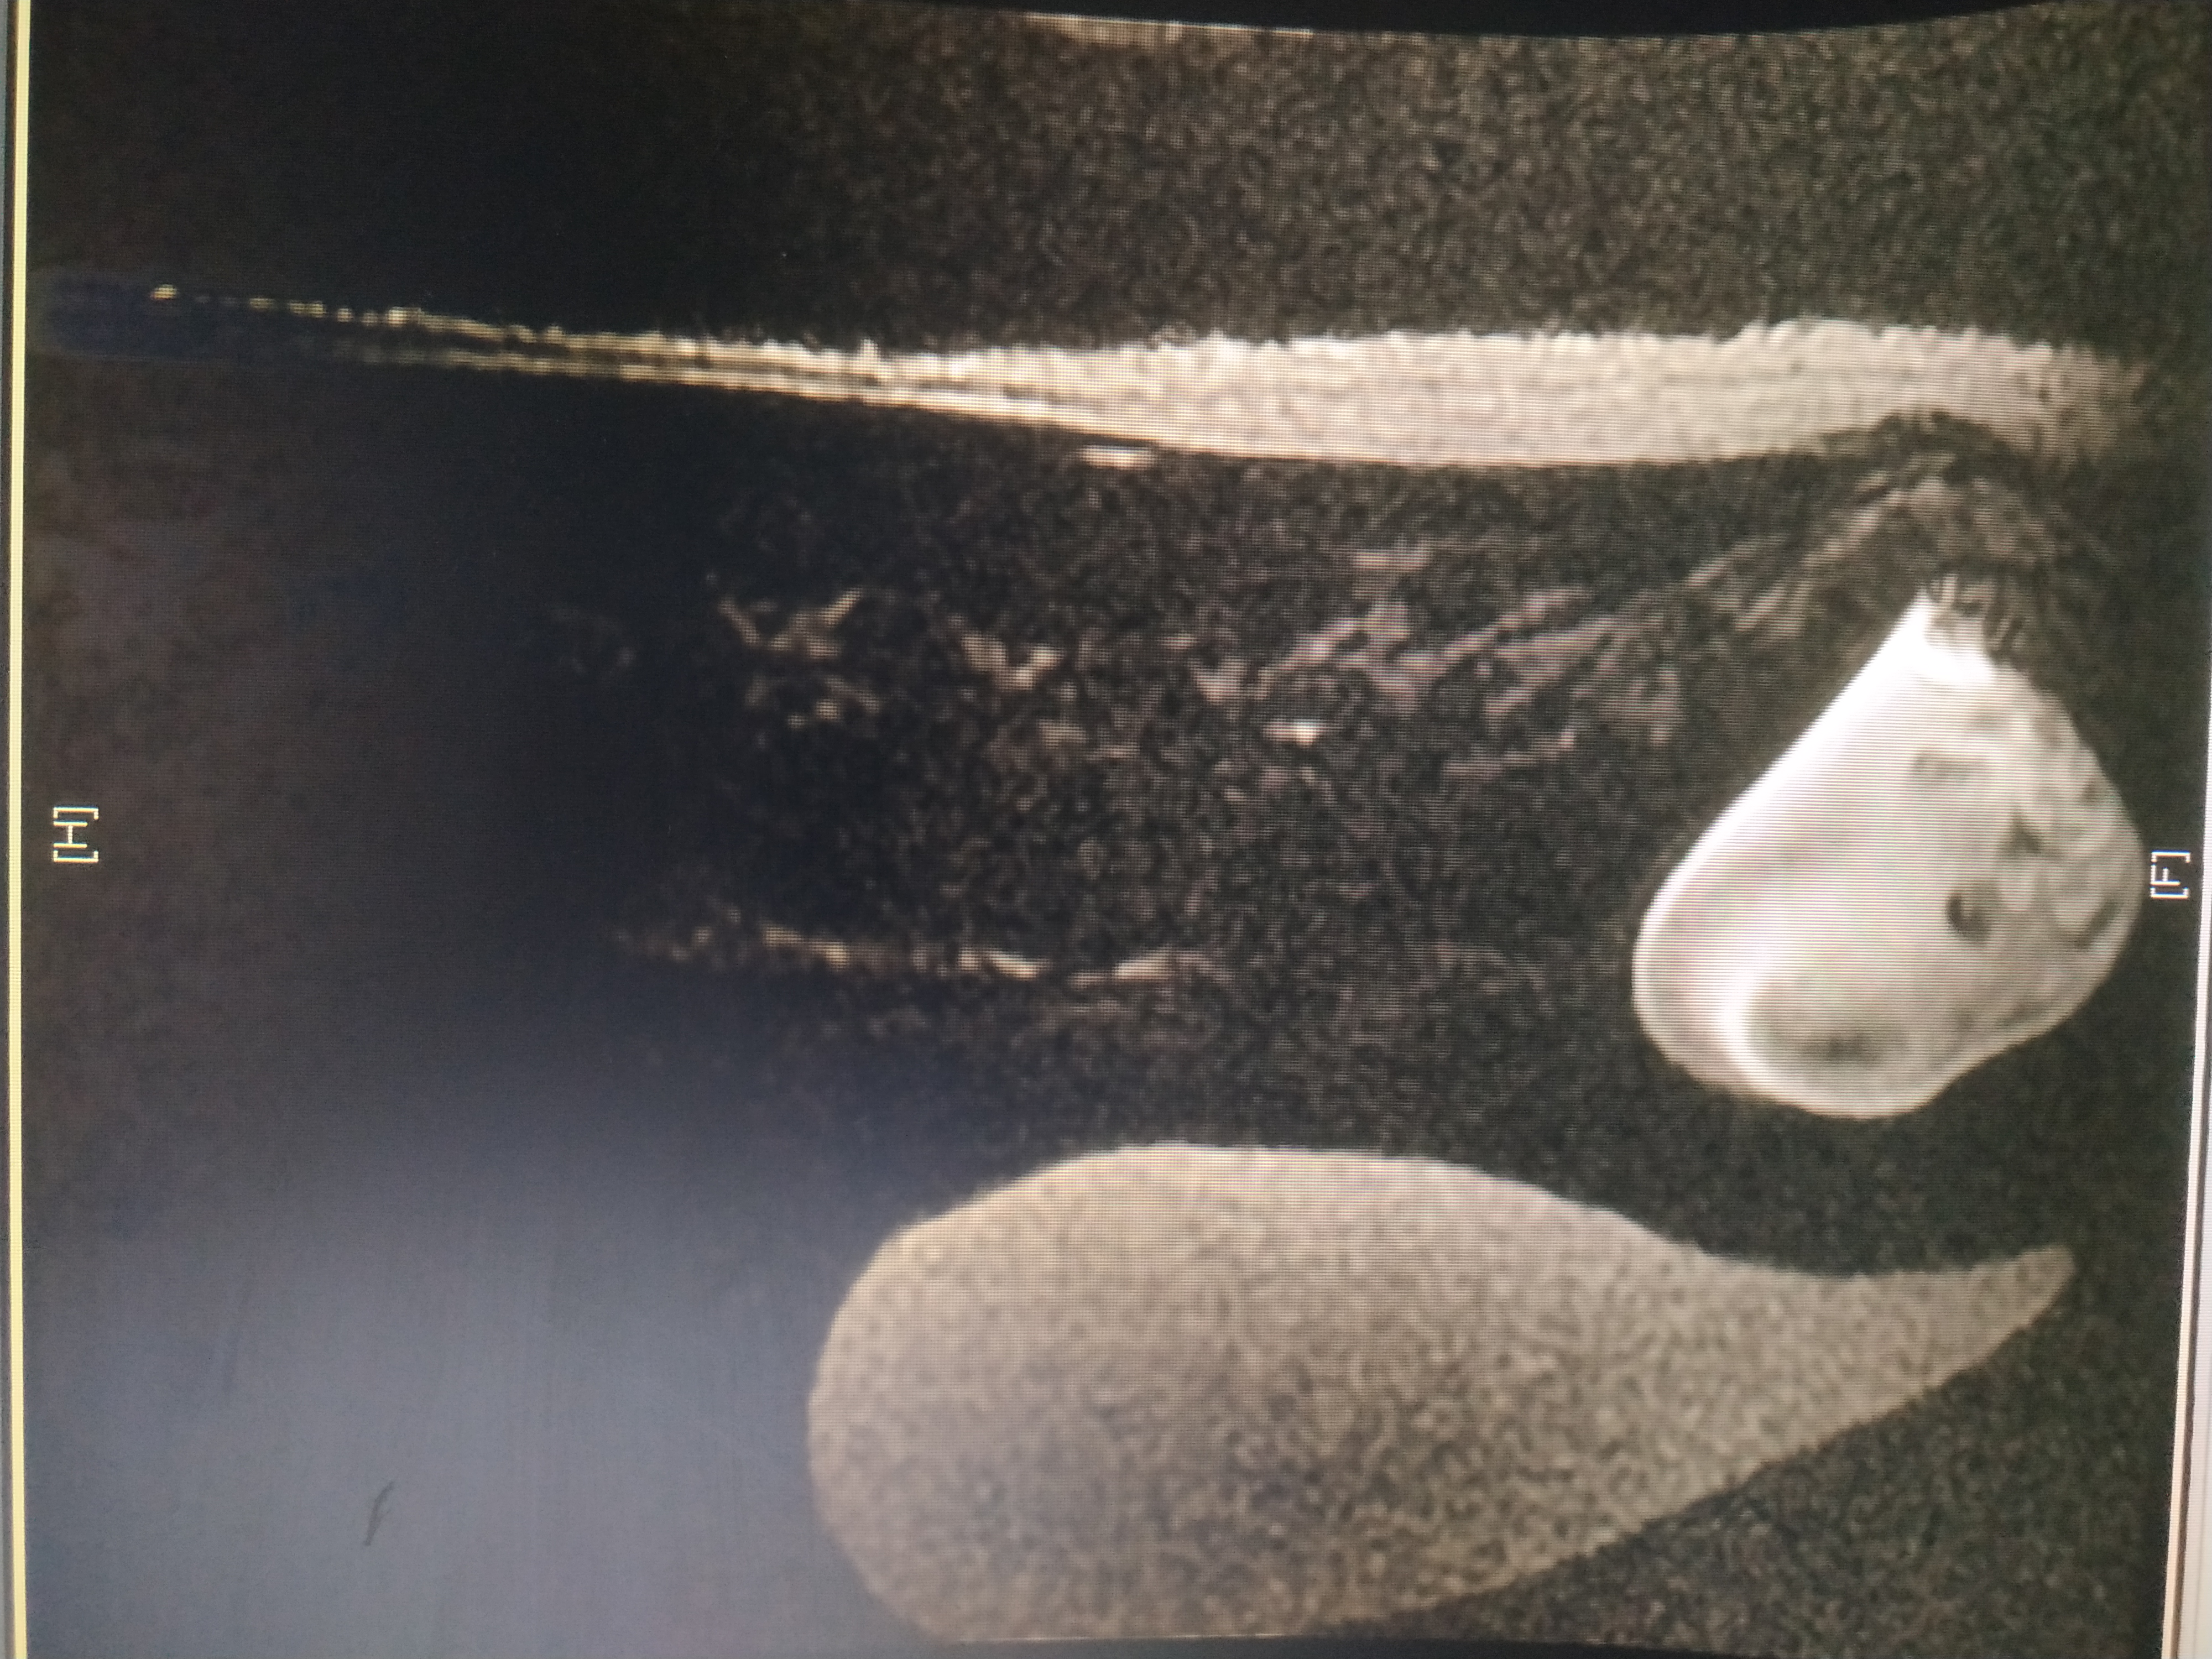

Здравствуйте! Скажите пожалуйста, оперировал ли кто нибудь из нейрохирургов в вашей клинике менингоцеле? Полный диагноз : менингоцеле крестцово - поясничного отдела s2-s5, Спинномозговая вентральная грыжа 11 см идущая в полость малого таза с компрессией мочевого пузыря, предстательной железы и дизурическими расстройствами. Мне 29 лет